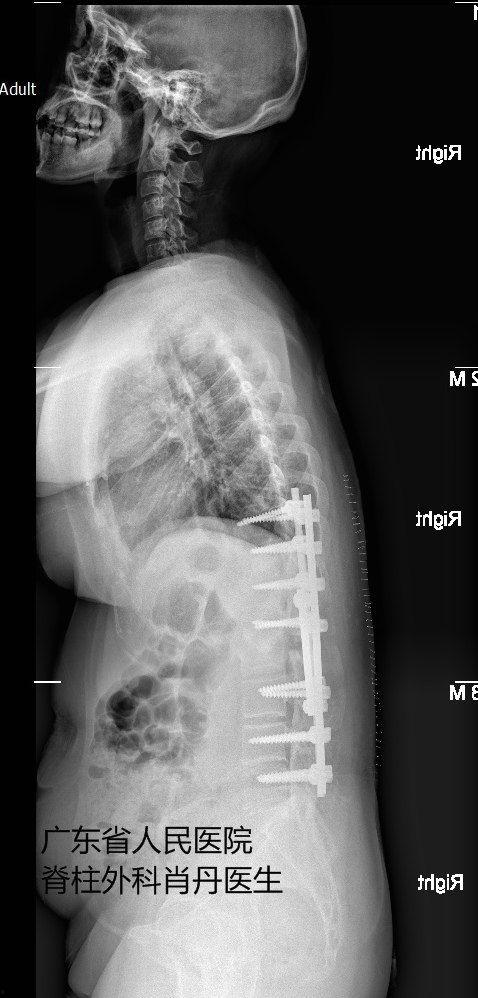

手术过程中,医生会根据患者的具体情况,选择合适的手术方式。常见的手术方法有:脊柱融合术、脊柱截骨术、脊柱侧弯矫正术等。这些手术都需要在全身麻醉下进行,患者将在无知觉的状态下完成这场与病痛的较量。

手术过程中,医生会小心翼翼地操作,尽量避免损伤周围的神经和血管。手术难度之大,可见一斑。正是这些勇敢的医生,用他们的精湛技艺,为患者带来了希望。